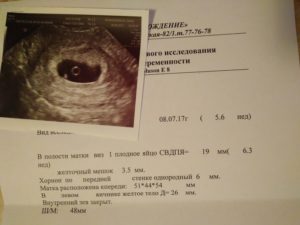

Когда видно плодное яйцо на УЗИ?

Но до определенного срока УЗИ обнаружить плод неспособно. Если говорить о том, во сколько недель можно определить беременность с помощью ультразвука, то плодное яйцо на УЗИ видно не раньше пятой-шестой недели.

Раньше этого срока на УЗИ еще не видно плодного яйца. До и на шестой неделе виден не эмбрион, а окружающий его желточный мешок, благодаря которому плод развивается.

Описание плодного яйца

Плодное яйцо — это защитные оболочки, окружающие зародыш. Они прикрепляются к стенке матки, образуя с ней сосудистую связь. Через сосуды растущий зародыш получает питание из материнской крови. Плодное яйцо на УЗИ выглядит, как округлое образование темно-серого цвета.

Оно становится видным, когда достигает размера 5 мм. Это соответствует 4 неделям беременности. Эмбрион внутри яйца пока не виден. Его можно рассмотреть после 35-го дня, выглядит он как темная полоска. Части его тела можно увидеть на 12 неделе беременности — в этот срок обычно и проводят первое обследование.

Размеры плодного яйца по неделям

По размерам зародыша определяют срок беременности с точностью до 2-3 дней. До полутора месяцев дату родов определяют по ДПП — диаметру плодного яйца. Диаметр измеряют в самой широкой части по трем разным плоскостям. Для вычисления даты родов есть специальная таблица.

Такой критерий, как СВД — средний внутренний диаметр — определяет дату родов не очень точно. После 6 недели, когда на УЗИ появляется эмбрион, срок определяют по КТР — копчико-теменной размер. Изображение эмбриона измеряют продольно. Размеры с 6 по 8 недели: